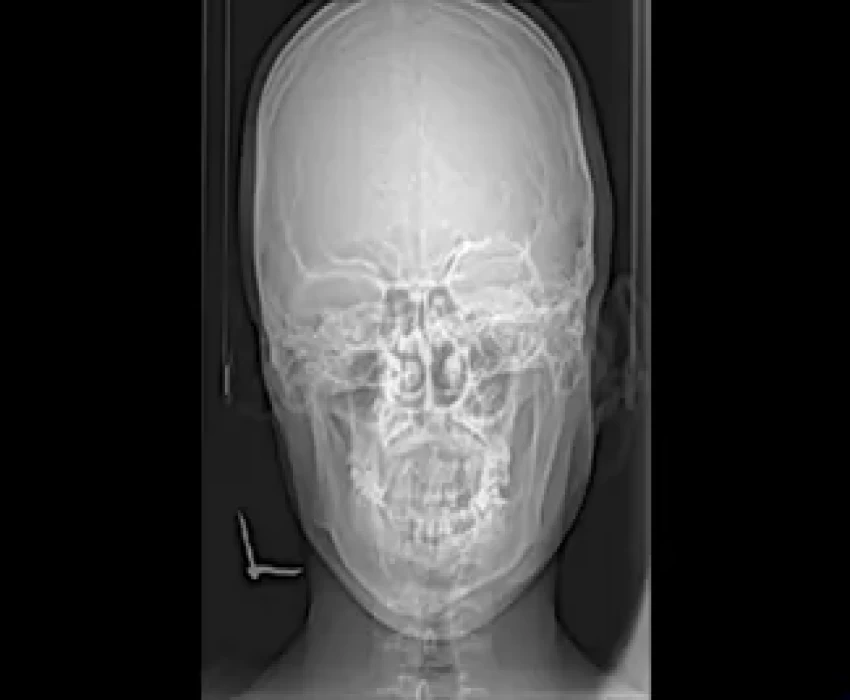

Following investigations were carried out

Radiographs